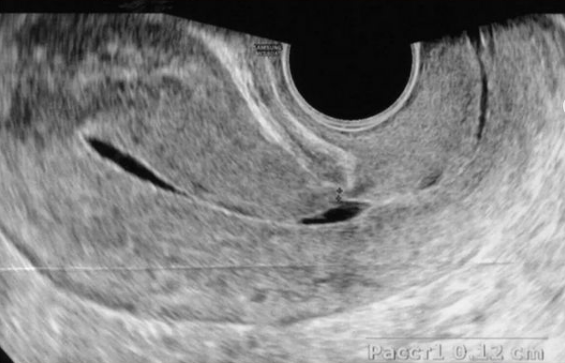

▪️К УЗ-признакам несостоятельности рубца на матке относят неровный контур по задней стенке наполненного мочевого пузыря, истончение миометрия, прерывистость контуров рубца, значительное количество гиперэхогенных включений.

Измеряют 3 размера ниши и толщину миометрия в области рубца. Толщина миометрия в области рубца менее 3 мм — абсолютное показание к хирургическому лечению, если женщина планирует забеременеть.